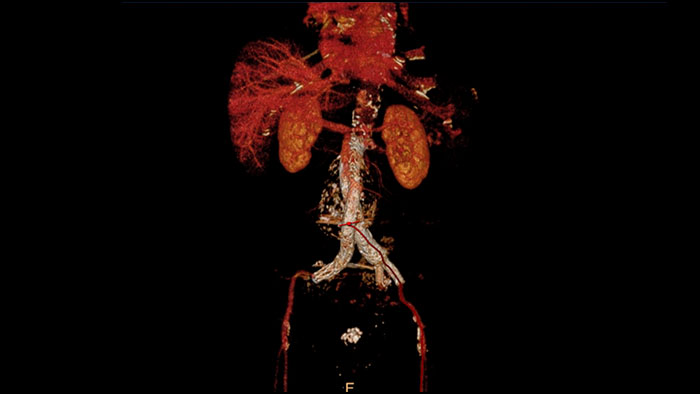

Endovascular stent placement

CT Advanced Vessel Analysis (AVA) Stent Planning includes multiple preset and user-defined options to gain detailed information for use in stent planning.

Benefits